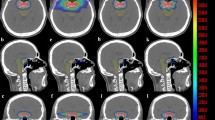

Figure 2 shows the distributions of the dosimetric parameters with regard to HI, CI, and GI for both treatment approaches. The HA-VMAT plans achieve a significantly higher HI (mean ± standard deviation (SD); 1.24 ± 0.07 (C-VMAT) vs. 1.41 ± 0.07 (HA-VMAT), p < 0.01) and CI (0.90 ± 0.05 (C-VMAT) vs. 0.93 ± 0.02 (HA-VMAT), p = 0.01). In addition, the HA-VMAT plans generate a significant rapid dose falloff (GI) when compared with that of the C-VMAT plans (3.91 ± 0.55 (C-VMAT) vs. 3.06 ± 0.42 (HA-VMAT), p < 0.01).

Boxplots of dosimetric parameters of homogeneity index (HI), conformity index (CI), and gradient index (GI) for conventional VMAT (C-VMAT) and HyperArc VMAT (HA-VMAT) plans. Boxes, median value and upper and lower quartiles; Whiskers, maximum and minimum values within 1.5 × inter-quartile range; Dots, outliers